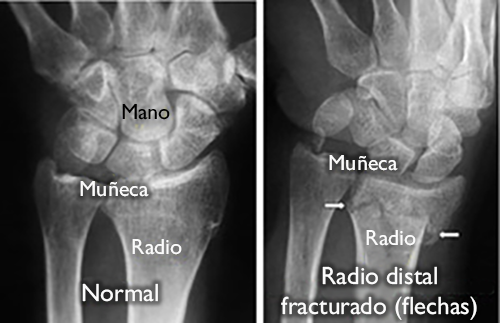

(Izquierda) Una radiografía de una muñeca sana. (Derecha) Las flechas blancas señalan una fractura de radio distal.